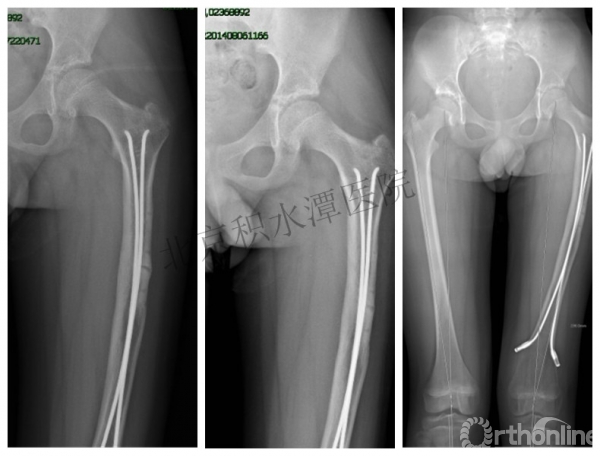

病例分享一

男孩 、5岁,初次骨折于2007年7月。

术后2年→再骨折→再次手术

钢板固定后一年

取板后再骨折→TEN

TEN取出后2个月

闭合复位再固定加尾帽

又过了4年!时间来到2015年